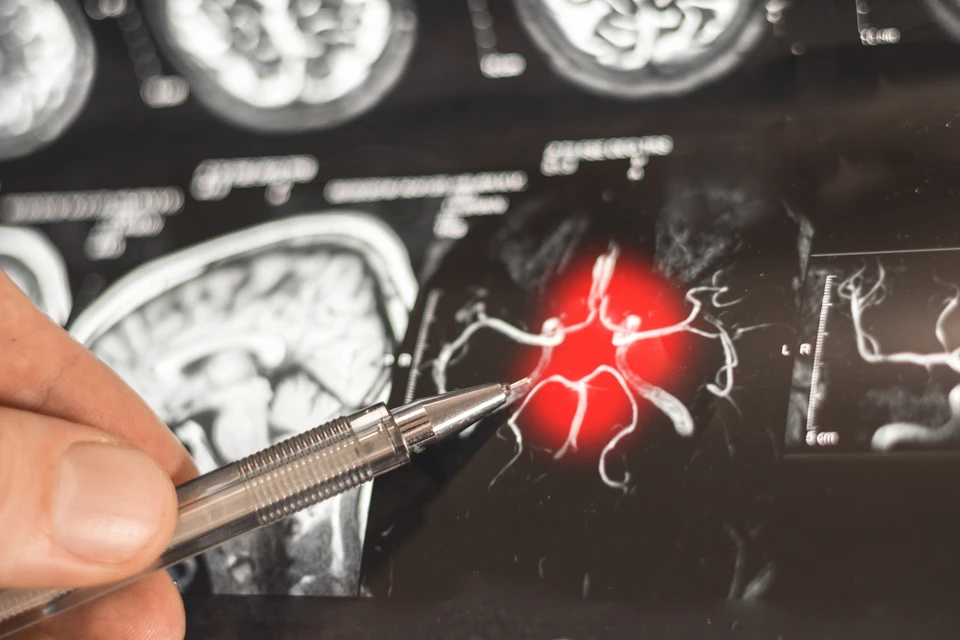

Фото: Only_NewPhoto/Shutterstock/Fotodom